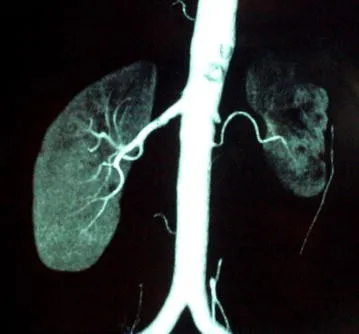

Este vídeo apresenta, de forma didática e baseada em evidências, os principais achados da tese de doutorado sobre amiloidose renal, com foco em proteômica glomerular e ativação do complemento. São discutidos aspectos diagnósticos, implicações fisiopatológicas e correlações clínico-patológicas relevantes para a prática do nefrologista. O conteúdo sintetiza dados inéditos de matriz extracelular glomerular e diferencia perfis entre subtipos de amiloidose. Trata-se de um material aprofundado e acessível, ideal para atualização de especialistas na área.